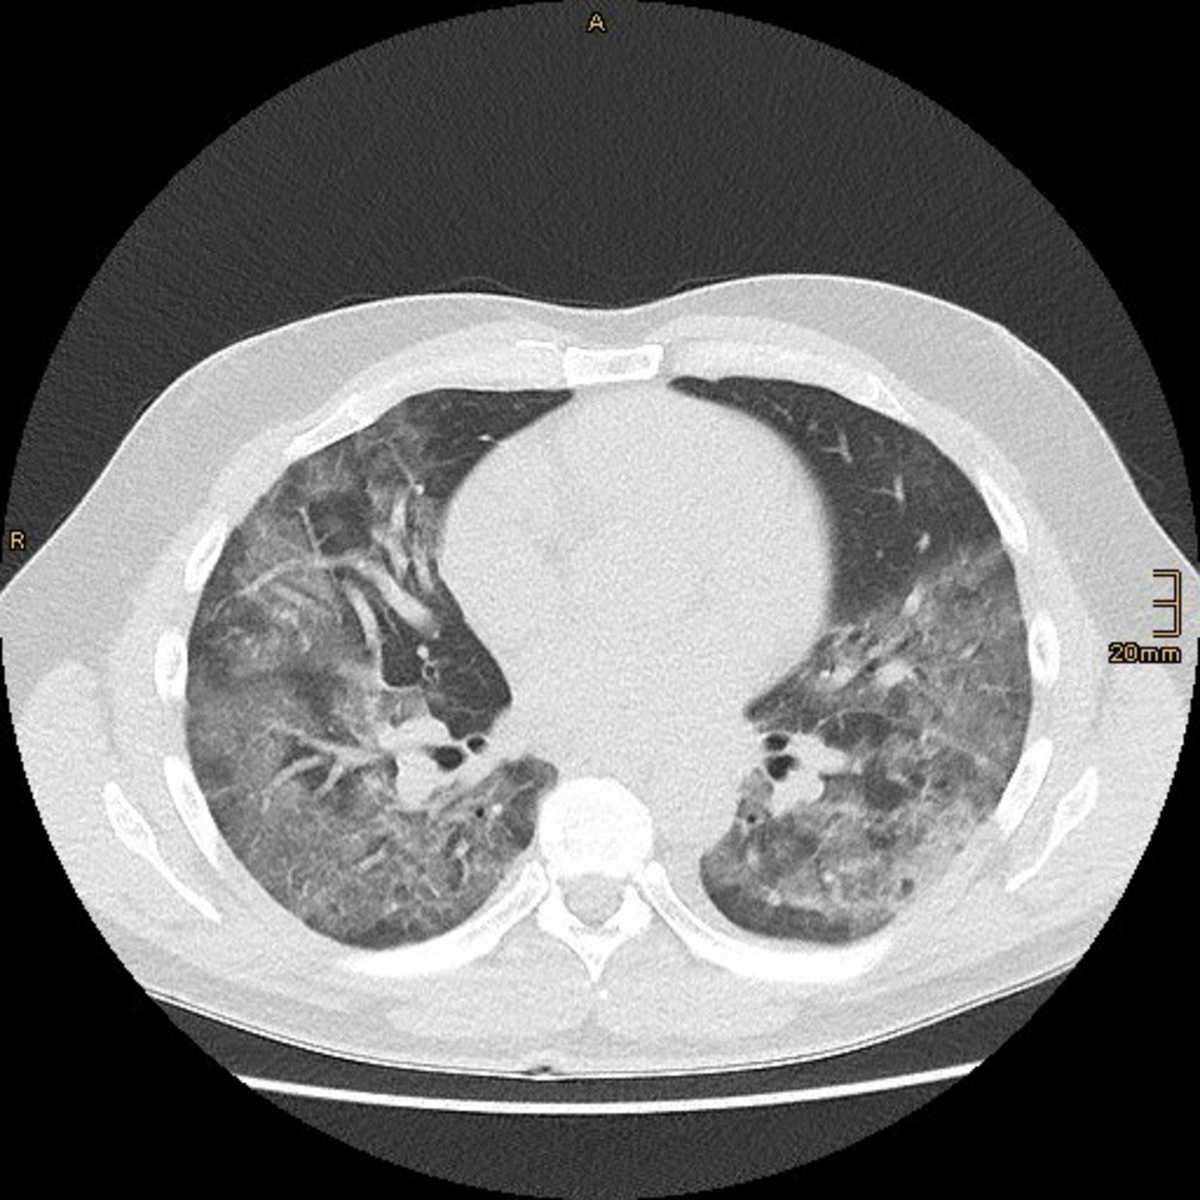

"I realised as soon as I saw the first CT scan ... that this had nothing to do with what we had seen and done for the past 40 years," he told Reuters.

In a paper published by the American Thoracic Society on March 30, Gattinoni and other Italian doctors wrote that COVID-19 does not lead to "typical" respiratory problems. Patients' lungs were working better than they would expect for ARDS, they wrote - they were more elastic. So, he said, mechanical ventilation should be given "with a lower pressure than the one we are used to."